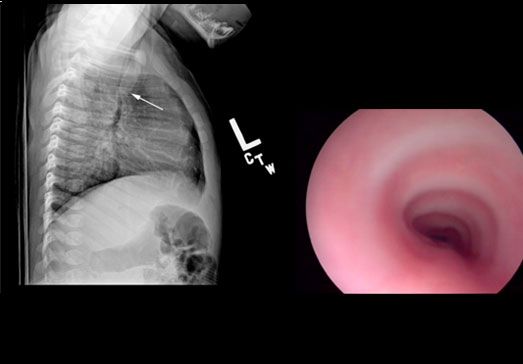

This week’s quiz questions challenge you to determine the cause of an infant’s “strange breathing” based on a chest film, to come up with the most common cause of chronic cough in children, to be a dermatologic detective, among other things.